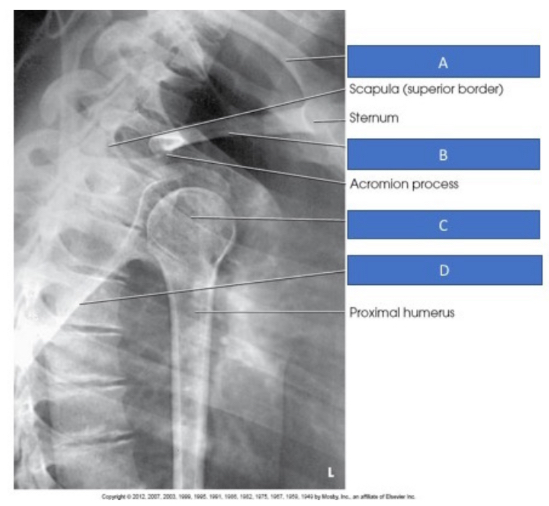

PA LAO Shoulder Y, Left